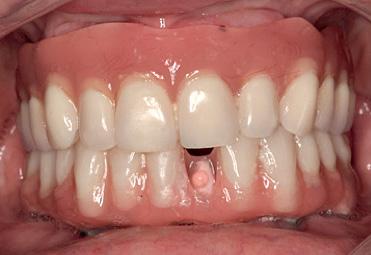

On discussion with the patient, keeping in mind the clinical and CBCT findings, the option of coronectomy was suggested for LL8 and RL8. If roots become loose during the procedure, then complete removal. The patient consented to have her wisdom teeth removed and coronectomies for the lower wisdom teeth under general anaesthesia.

A standard coronectomy technique for removal of RL8 tooth was carried out. Lingual periosteum was not reflected to avoid lingual nerve injury. Following sectioning and trimming of the tooth until the cementoenamel junction (CEJ), there was insufficient soft tissue to achieve primary closure of the socket.

The decision on which abutment is best for your patient – conical or platform – is yours.

To achieve good primary closure, it was decided to modify the procedure and trim the roots up to the furcation to ensure a sound collar of alveolar bone and advance the buccal flap. This modification helped significantly during primary closure of the socket. LL8 tooth was removed completely as the roots became loose as well as UR8 and LU8. The post-operative phase was uneventful, and she recovered well (Fig 4).